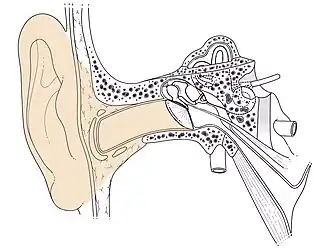

Conduit auditif externe humain

Cet article ne traite que l'anatomie humaine. Le conduit auditif externe, appelé aussi canal auriculaire ou méat acoustique externe, est la partie de l'oreille externe, située entre le pavillon et le tympan.

C'est un canal ostéocartilagineux mesurant de 25 mm de long et de 8 à 10 mm de diamètre, qui dans le plan horizontal présente une double courbure en « S », dans le plan vertical il est ascendant puis descendant à partir de l'isthme du conduit (partie rétrécie médiane). Sa forme générale est celle d'un cylindre aplati d'avant en arrière.

Conduit auditif externe droit Schéma